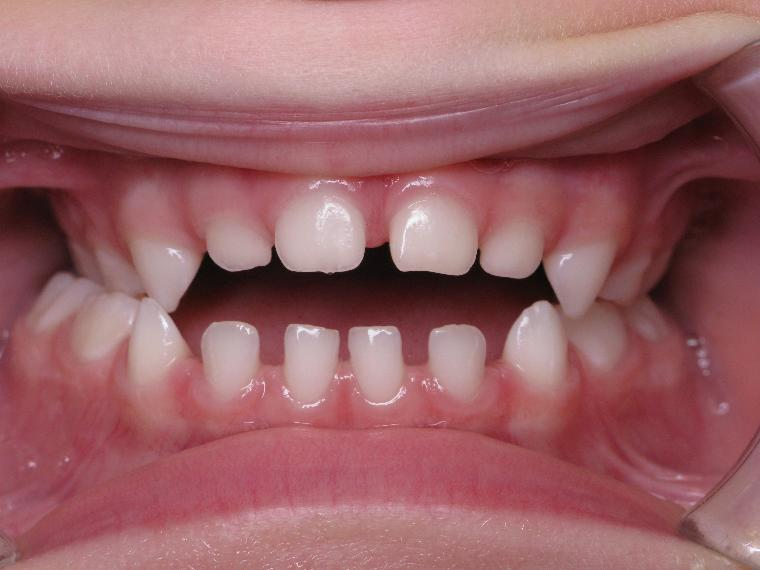

inversion postérieur coté droit et espace entre les dents du haut et du bas (diastèmes)

bilan début et en cours de traitement